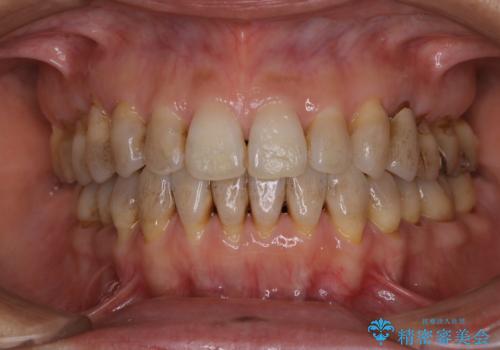

30代男性 PMTCで歯石取り

担当医 歯科衛生士